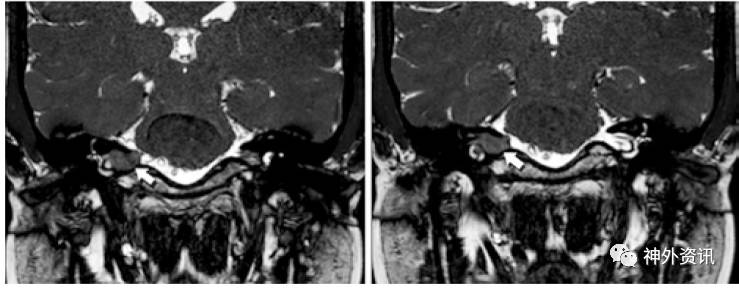

从2011年11月至2015年1月,在上述两家医院有10例患者接受EETTA入路切除位于内听道内的听神经瘤或脑膜瘤。该入路的手术指征为,①MRI成像提示进行性增大的听神经瘤;②肿瘤分级为Koos Grade I级(肿瘤局限于内听道内)(图1)或Koos Grade II级(肿瘤局部涉及小脑桥脑角);③美国耳鼻喉头颈外科学会(AAO-HNS)听力分级D级,即严重听力丧失。所有手术均由两位耳鼻喉科主任医师主刀,1名神经外科医师做助手。图2、3、4、5展示手术图解和术中照片。

图1. MRI-T2加权冠状位显示内听道内听神经瘤,未向小脑桥脑角区扩展(白色箭头)。